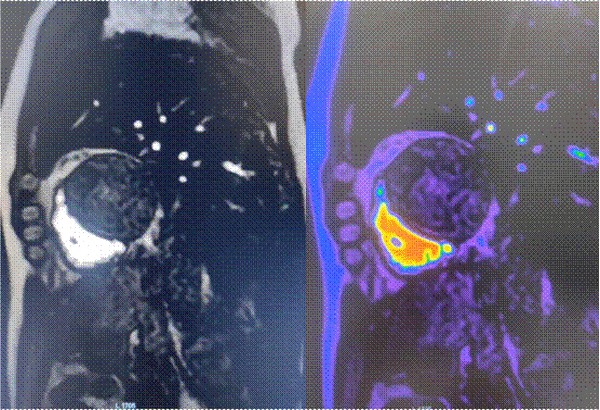

心脏灌注成像